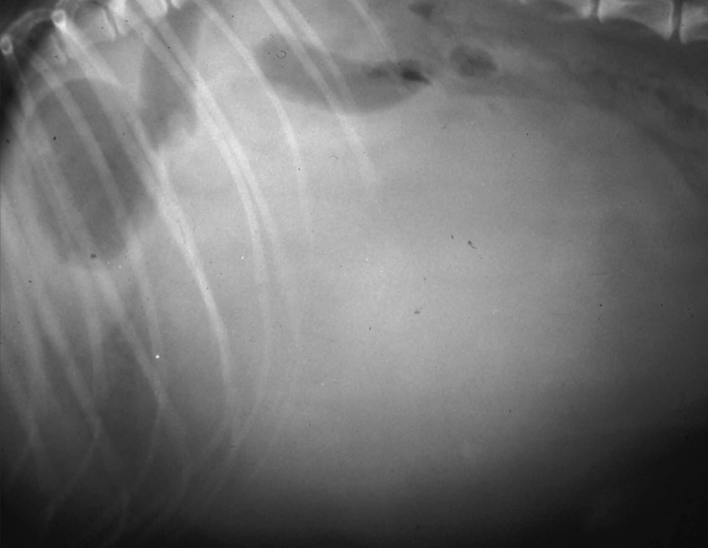

xrays of hemoabdomen can show

A

• Loss of abdominal detail

• Small intestinal displacement

• Lack of normal splenic position

• Occasionally gas within the spleen

ultrasound usually more helpful